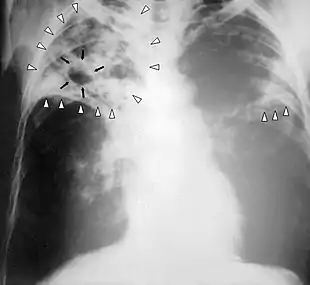

Tuberculosis (TB), also known colloquially as the "white death", or historically as consumption,[7] is an infectious disease usually caused by Mycobacterium tuberculosis (MTB) bacteria.[1] Tuberculosis generally affects the lungs, but it can also affect other parts of the body.[1] Most infections show no symptoms, in which case it is known as latent tuberculosis.[1] Around 10% of latent infections progress to active disease which, if left untreated, kill about half of those affected.[1] Typical symptoms of active TB are chronic cough with blood-containing mucus, fever, night sweats, and weight loss.[1] Infection of other organs can cause a wide range of symptoms.[8]

If a tuberculosis infection does become active, it most commonly involves the lungs (in about 90% of cases).[15][18] Symptoms may include chest pain and a prolonged cough producing sputum. About 25% of people may not have any symptoms (i.e., they remain asymptomatic).[15] Occasionally, people may cough up blood in small amounts, and in very rare cases, the infection may erode into the pulmonary artery or a Rasmussen's aneurysm, resulting in massive bleeding.[8][19] Tuberculosis may become a chronic illness and cause extensive scarring in the upper lobes of the lungs. The upper lung lobes are more frequently affected by tuberculosis than the lower ones.[8] The reason for this difference is not clear.[14] It may be due to either better air flow,[14] or poor lymph drainage within the upper lungs.[8]